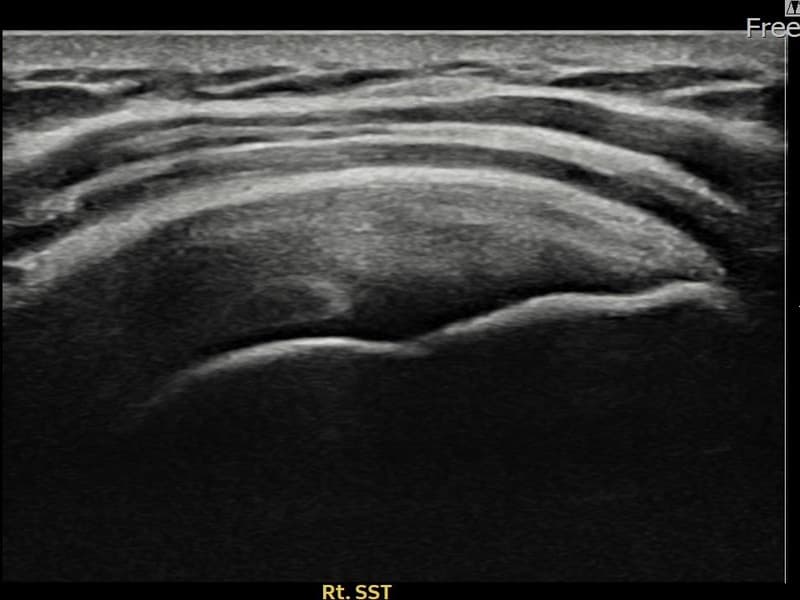

术后

术前超声确认右侧 견갑하근건 部分撕裂,右侧冈上肌腱回声不连续伴肌腱缺损(8mm × 3mm (肌腱厚度约32%缺损))。术后超声显示撕裂部位充满再生组织,肌腱连续性恢复,回声模式正常化。

该患者持续肩痛。详细超声检查确认右侧 견갑하근건 部分撕裂(缺损:8mm × 3mm (肌腱厚度约32%缺损))。在超声引导下实施非手术缩小缝合术。术后佩戴支具约4-6周,随后进行分阶段康复锻炼。随访超声确认肌腱连续性恢复、结构稳定,患者顺利回归日常生活。